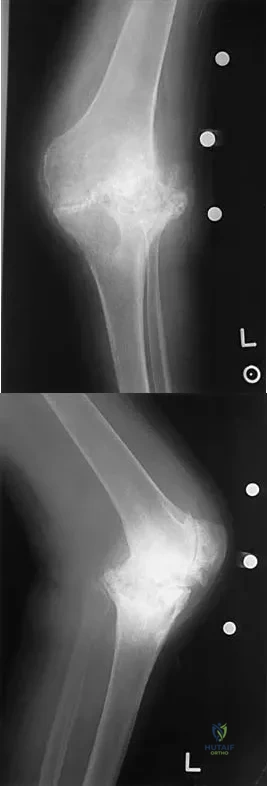

Question 67

A 65-year-old man has a painful and often audible crepitus after undergoing a total knee arthroplasty 8 months ago. His symptoms are reproduced with active extension of about 30 degrees. Examination reveals no effusion or localized tenderness, a stable knee, and a range of motion of 5 degrees to 120 degrees. Radiographs are shown in Figures 37a and 37b. Management should consist of

Explanation